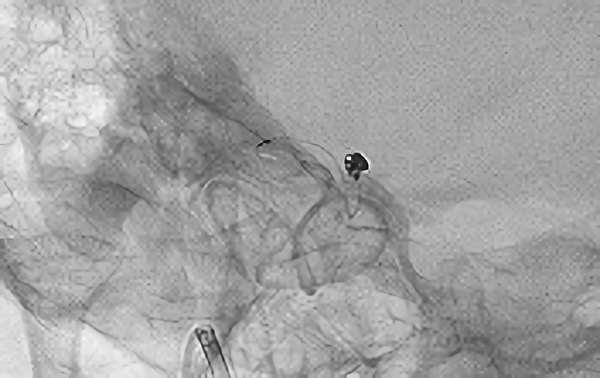

'26年4月

左内頚動脈脳動脈瘤

70代

大阪府の病院

No.1630 手術前